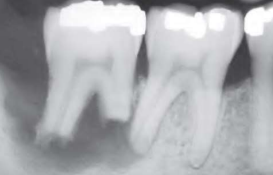

Periapical(radicular) cysts | Rest of Malassez 被刺激 | - | - | true/ periapical cyst 圓形的光通性包圍根尖 |

牙根吸收, 2cm ↑ 根管治療無效 ![]() |